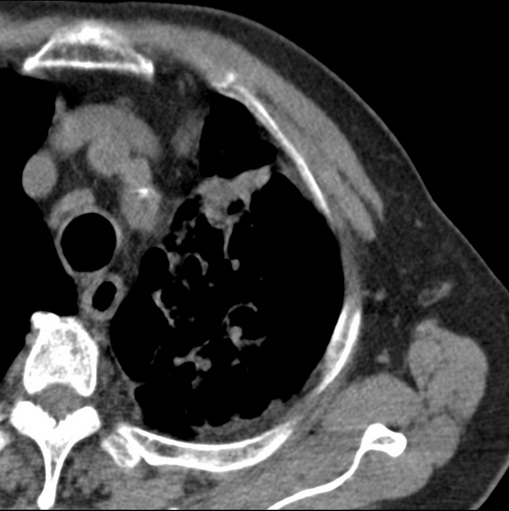

标题: CT25434:胸部CT增强扫描

男性患者 81岁 咳嗽 咳痰 咯血

左肺中心型肺癌并:1.左肺阻塞性肺炎;2.纵隔淋巴结肿大;

肿块贴近左肺门,包绕左上肺动脉,形态不规则。肿块增强扫描中度强化。纵膈内主动脉弓左旁间隙、气管隆突前、下间隙见多枚淋巴结影。综上考虑左侧中央型肺癌可能性大。图片没有完整上传,尤其是左肺上叶支气管分支层面没有上传,因此不好判断是叶支气管中断还是段支气管中断。另外,下图红色部分所示是“黏液支气管征”吗?